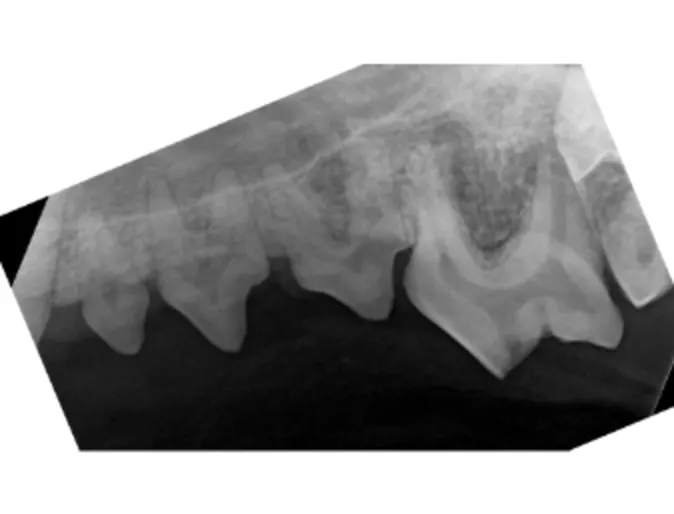

Notice there is bone reaching all the way to the crown of the tooth, indicating NO bone loss.

Notice how gums have a sharp edge and lay flat against the tooth. This is healthy gums look.